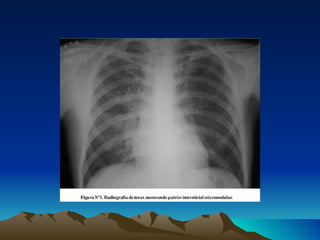

NAC-Diagnostico Cuadro clinico (F, DT, D, T, E) Exploracion fisica (S. Consolidacion) Radiografia de torax: Patron alveolar:  neumonia alveolar, lobar, basal o segmentaria. Opacidad homogenea con broncograma aereo.  Neumonia neumococica.  Cualquier neumonia bacteriana. Patron de bronconeumonia:  neumonia bronconeumonica. Imagenes radiologicas de focos multiples en ambos campos pulmonares.  Neumonia estafilococica, enterobacterias.  Por via hematogena. Patron intersticial:  disociacion clinico-radiologico, neumonias atipicas.  M. Pneumoniae, Clamidias y virus.

NAC-Diagnostico Cuadro clinico(F, DT, D, T, E) Exploracion fisica (S. Consolidacion) Radiografia de torax: Patron alveolar: neumonia alveolar, lobar, basal o segmentaria. Opacidad homogenea con broncograma aereo. Neumonia neumococica. Cualquier neumonia bacteriana. Patron de bronconeumonia: neumonia bronconeumonica. Imagenes radiologicas de focos multiples en ambos campos pulmonares. Neumonia estafilococica, enterobacterias. Por via hematogena. Patron intersticial: disociacion clinico-radiologico, neumonias atipicas. M. Pneumoniae, Clamidias y virus.